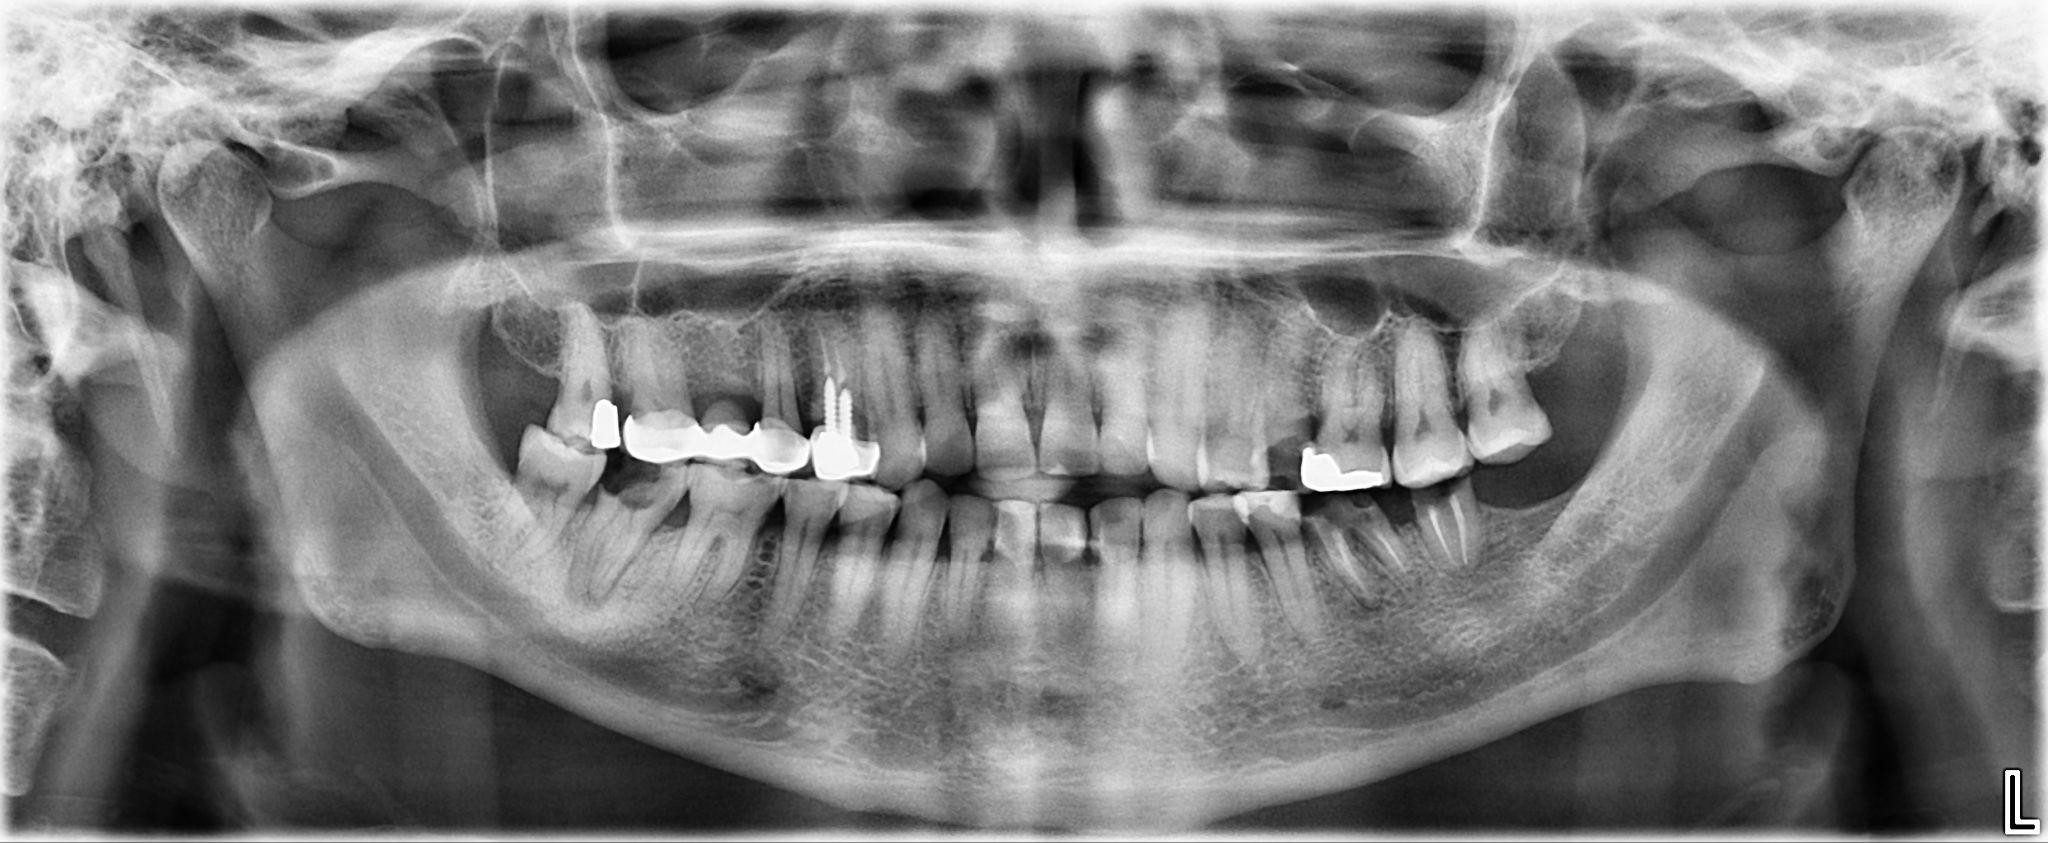

5. What option cannot be selected for the first quadrant of this panoramic X ray?

6 / 25

6. What option cannot be selected for the third quadrant of this panoramic X ray?

7 / 25

7. What option cannot be selected for the forth quadrant of this panoramic X ray?